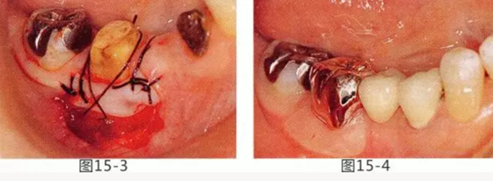

圖15-3 切除系帶。為了獲得附著齦,進行游離齦移植。

圖15-4 手術完成6個月后,佩戴修復體時的狀態(tài)。